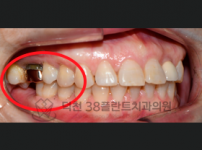

치료전후